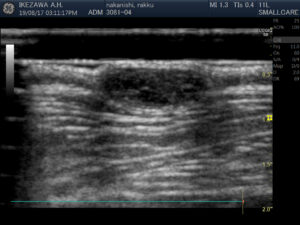

皮膚エコーは、高周波エコーで皮膚を診る検査です。よく使うのは皮膚にしこりができていたり、強く腫れている時に使います。下の写真が皮膚エコーの写真です。(別の患者さんの画像です)

(黒い塊が皮膚にできたしこりです。比較的輪郭がはっきりとしたしこりである事がわかります。)

皮膚エコーの特徴は、皮膚表面からは見えない皮膚の奥の様子を確認する事ができる、という事です。しこりがどこにあって、どこまで広がっているのか。しこりは均一な組織なのか、いろんな細胞が入り混じるような複合的な組織なのか。いろんな情報がわかってきます。